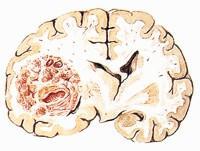

顱內黑色素瘤病理圖黑色素細胞瘤可由表皮黑色素細胞,痣細胞或真皮成黑色素細胞組成。腫瘤起源於外胚葉的神經嵴,黑色素細胞位於表皮層與基底細胞間排列,細胞產生色素後,通過樹狀突將黑色素顆粒輸送到基底細胞和毛髮內。

單純病理組織學檢查很難確定顱內黑色素瘤為原發性或繼發性。因兩者在組織形態學上基本一致。腫瘤呈灰黑色因腫瘤部位不同形態不一。腦內腫瘤常呈結節狀,界線尚清,腦膜或近皮層的腫瘤呈瀰漫或地毯狀。若近顱底常包繞周圍腦神經,造成多發性腦神經損害,侵及脊髓者常伴有相應節段的脊髓神經根症狀。顯微鏡檢查可見瘤細胞呈梭形或多角形,胞核呈圓形或卵圓形,常被色素掩蓋或擠向一側,很少有核分裂現象。胞質內有顆粒狀或塊狀的黑色素,瘤細胞無一定排列方式,在蛛網膜下腔聚集成堆,或沿血管向外延伸顱內黑色素瘤無論在組織發生、形態及生物學行為等方面,均難與黑色素型腦膜瘤相區別。